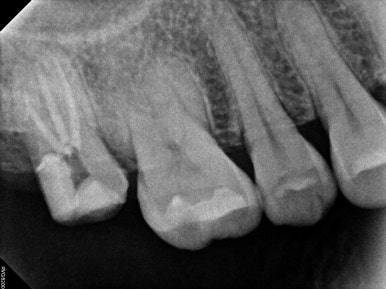

제가 여기서 임플란트 치료 잘 되었는지 확인하는 법을 대략적으로 알려드릴께요!

생각보다 이렇게 제작되어 있는 임플란트가 많지 않습니다. 특히 보다 더 비싼 맞춤형 지대주 (custom abutment)를 사용하지 않고 기성 지대주를 사용하면 이렇게 자연스러운 형태가 되기가 힘듭니다.

주변 뼈 높이에 잘 맞게 임플란트가 심겨있어야 합니다. 너무 깊어도 얕아도 좋지 않죠. 노란색 선이 잇몸뼈 높이를 표시한 것입니다.

임플란트 고정체 (fixture) 그리고 나머지의 비율이 1:1이 넘어가지 않는게 좋습니다. 너무 얕은 땅에 긴 전봇대가 심겨있다고 생각해보시면.. 불안하죠 뭔가?

임플란트 크라운의 중간에 임플란트 고정체가 위치해 있는게 이상적입니다. 상황에 따라 달라질 순 있겠지만, 아무래도 임플란트의 뿌리가 머리의 가운데에 있는게 좋겠죠. 츄파춥스 처럼요.

결론은 어쨌든 임플란트가 아~주 이상적으로 잘 제작되었다는 뜻!